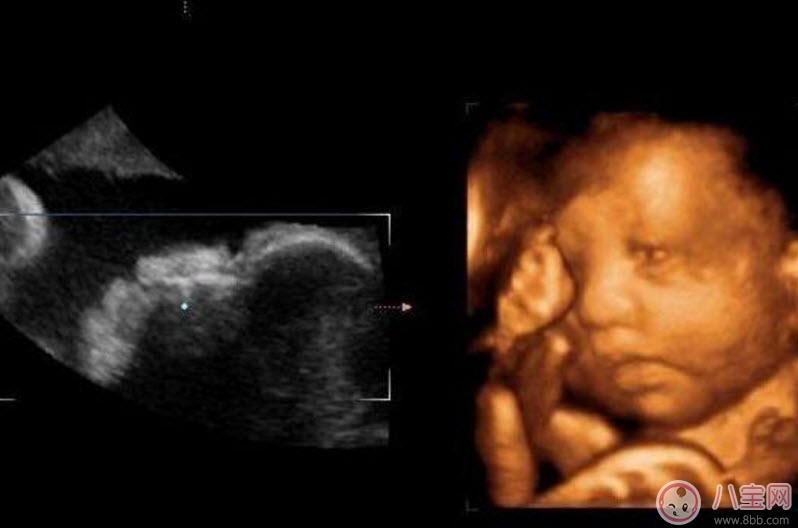

四維彩超的全稱是四維彩色超聲診斷儀,是世界上最先進的彩色超聲設備。四維彩超能夠表面成像,可以更佳清晰的查出來胎兒的四肢發(fā)育是否畸形,腦膜膨出,是否唇腭裂、脊柱裂等先天畸形,及早發(fā)現(xiàn)及早的做出解決方案。

二維超聲可以理解為我們通常說的B超,顯示的是斷面圖像。何為斷面圖像?就是把西瓜切開,你在屏幕上只能看到西瓜的切面(斷面),但經(jīng)驗豐富的你,可以只看這個切面(斷面)就知道這是一個西瓜。

三維、四維超聲就是把很多個二維斷面圖像通過計算機重建成一個立體的圖像。相當于把切成很多片的西瓜,重新堆疊成一個完整的西瓜,這個堆疊過程由計算機完成。三維、四維的區(qū)別在于,三維是照片,四維是影片,四維就是會動的三維照片(實時三維)。